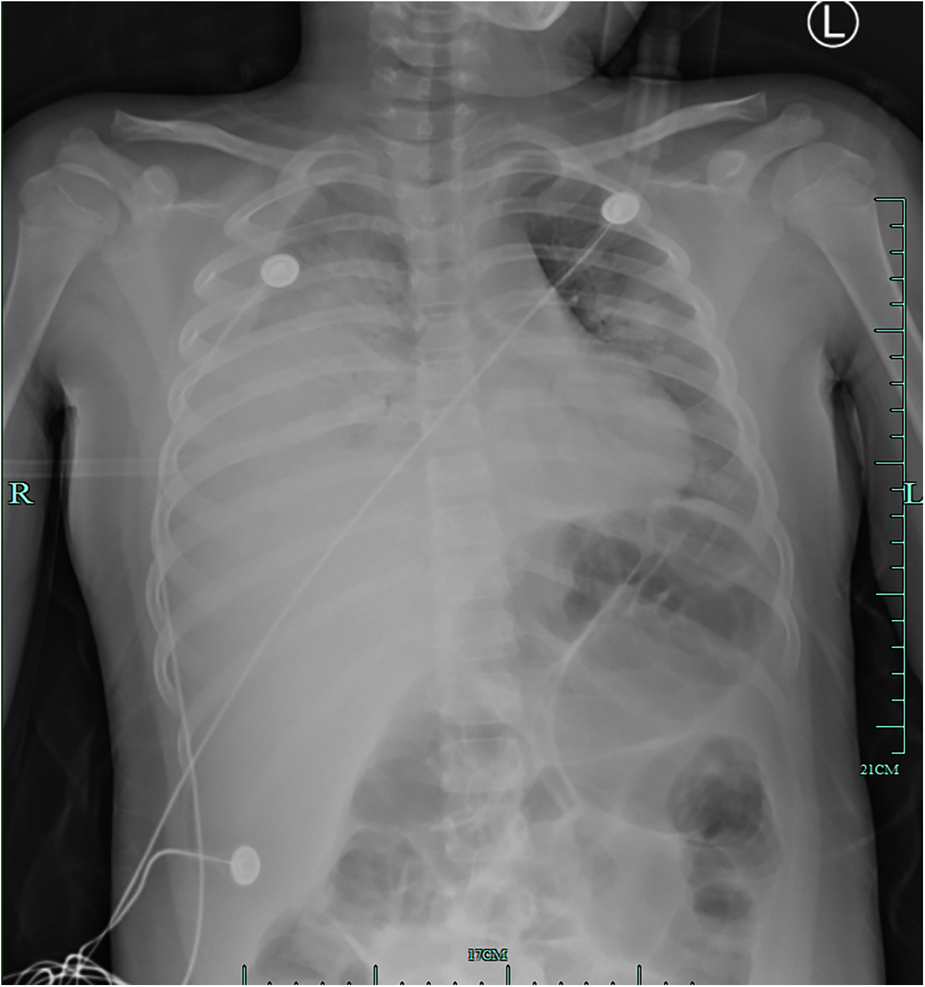

An 8-year-old girl presented to a hospital pediatric emergency department with a 1-week history of cough, fever for 4 days, and dyspnea for 5 h, without any response to oral cephalosporins. When she was admitted to the hospital, she had shortness of breath, 50 beats per minute, fever, 38.3 °C, tachycardia, 154 beats per minute, and hypoxemia, 72% in ambient air. Physical examination revealed moist rales in the left lung and diminished breath sounds over the right lung. Leukocyte count was 19 × 109/L, indicating leukocytosis of mainly neutrophils, and C-reactive protein level was 0.2 mg/dl. Blood biochemical analysis showed that the level of alanine aminotransferase was 516 U/L, lactate dehydrogenase was 2113 U/L, and sodium ions was 122 mmol/L. Chest x-ray photograph showed diffuse opacification on the left lung, Atelectasis was observed in the right lung with a large effusion in the right pleural cavity (Figure 1). She received a combination of antibiotics (azithromycin and ceftriaxone) to treat severe pneumonia and was transferred to the pediatric intensive care unit (PICU) for further treatment. There, she was given high-flow warm humidified oxygen through the nose. A computed tomography (CT) scan of the chest showed bilateral lung infection and right lung consolidation density; Multiplelymph nodes in the mediastinum show that the area is slightly larger; Bilateral pleural effusion (Figure 2A). Ultrasonic examination also showed a large amount of pleural effusion in the right lung. Lower chest puncture drainage was performed under ultrasound guidance, and antibiotic therapy was escalated to cefoperazone sodium, sulbactam sodium, and azithromycin. Analysis of pleural effusion showed that a protein level of 38.2 g/L, glucose of 6.57 mmol/L, lactate dehydrogenase of 3082 U/L, and mononuclear phagocyte predominance was observed. Negative bacterial culture results for blood, endotracheal aspirate and pleural effusion. Antigen testing for respiratory pathogens (including adenovirus, respiratory syncytial virus, influenza virus and EB virus) is suggestive of negative results. Polymerase chain reaction (PCR) showed that MP was positive in endotracheal aspirate and pleural effusion. MP-specific IgM and IgG antibodies from blood showed negative results. Acquired mutations on the ribosomal macrolide target were negative, suggesting that it was not a macrolide-resistant strain. Further medical history obtained from family members did not indicate any risk factors for tuberculosis; however, a gamma release assay was also sent for analysis. On the first day of admission, patient was found to have abnormal coagulation function, and bleeding spots appear on the skin the next day. In the coagulation profile, the international normalized ratio was 1.67, with a partial thromboplastin time of 31.5 s and a prothrombin time of 17.5 s. Thrombin time was 60.0 s. The fibrinogen function K value was 18.1 min, the fibrinogen and platelet function (angle) were 27.9, the platelet function was 21.2 mm, and the comprehensive index of coagulation function was −14.5. In order to exclude hematologic diseases, coagulation factors and plasma correction tests were added, and fresh frozen plasma and fibrinogen infusions were given, and the coagulation function was slightly improved. After 48 h, she remained febrile with worsening tachypnea and hypoxic respiratory failure, hemoptysis, and required intubation and ventilation. Blood was visible in the airway, and bronchoscopy and bronchoalveolar lavage revealed DAH. Therefore, a diagnosis of severe MP in conjunction with DAH, severe pediatric acute respiratory distress syndrome (ARDS), and acute hypoxic respiratory failure was established. Human blood immunoglobulin, epinephrine endotracheal instillation, and intravenous application of glucocorticoids were administered.

Figure 1

Initial chest radiograph on hospitalization day 1 showing diffuse opacification on the left lung, atelectasis in the right lung, and a large effusion in the right pleural cavity.